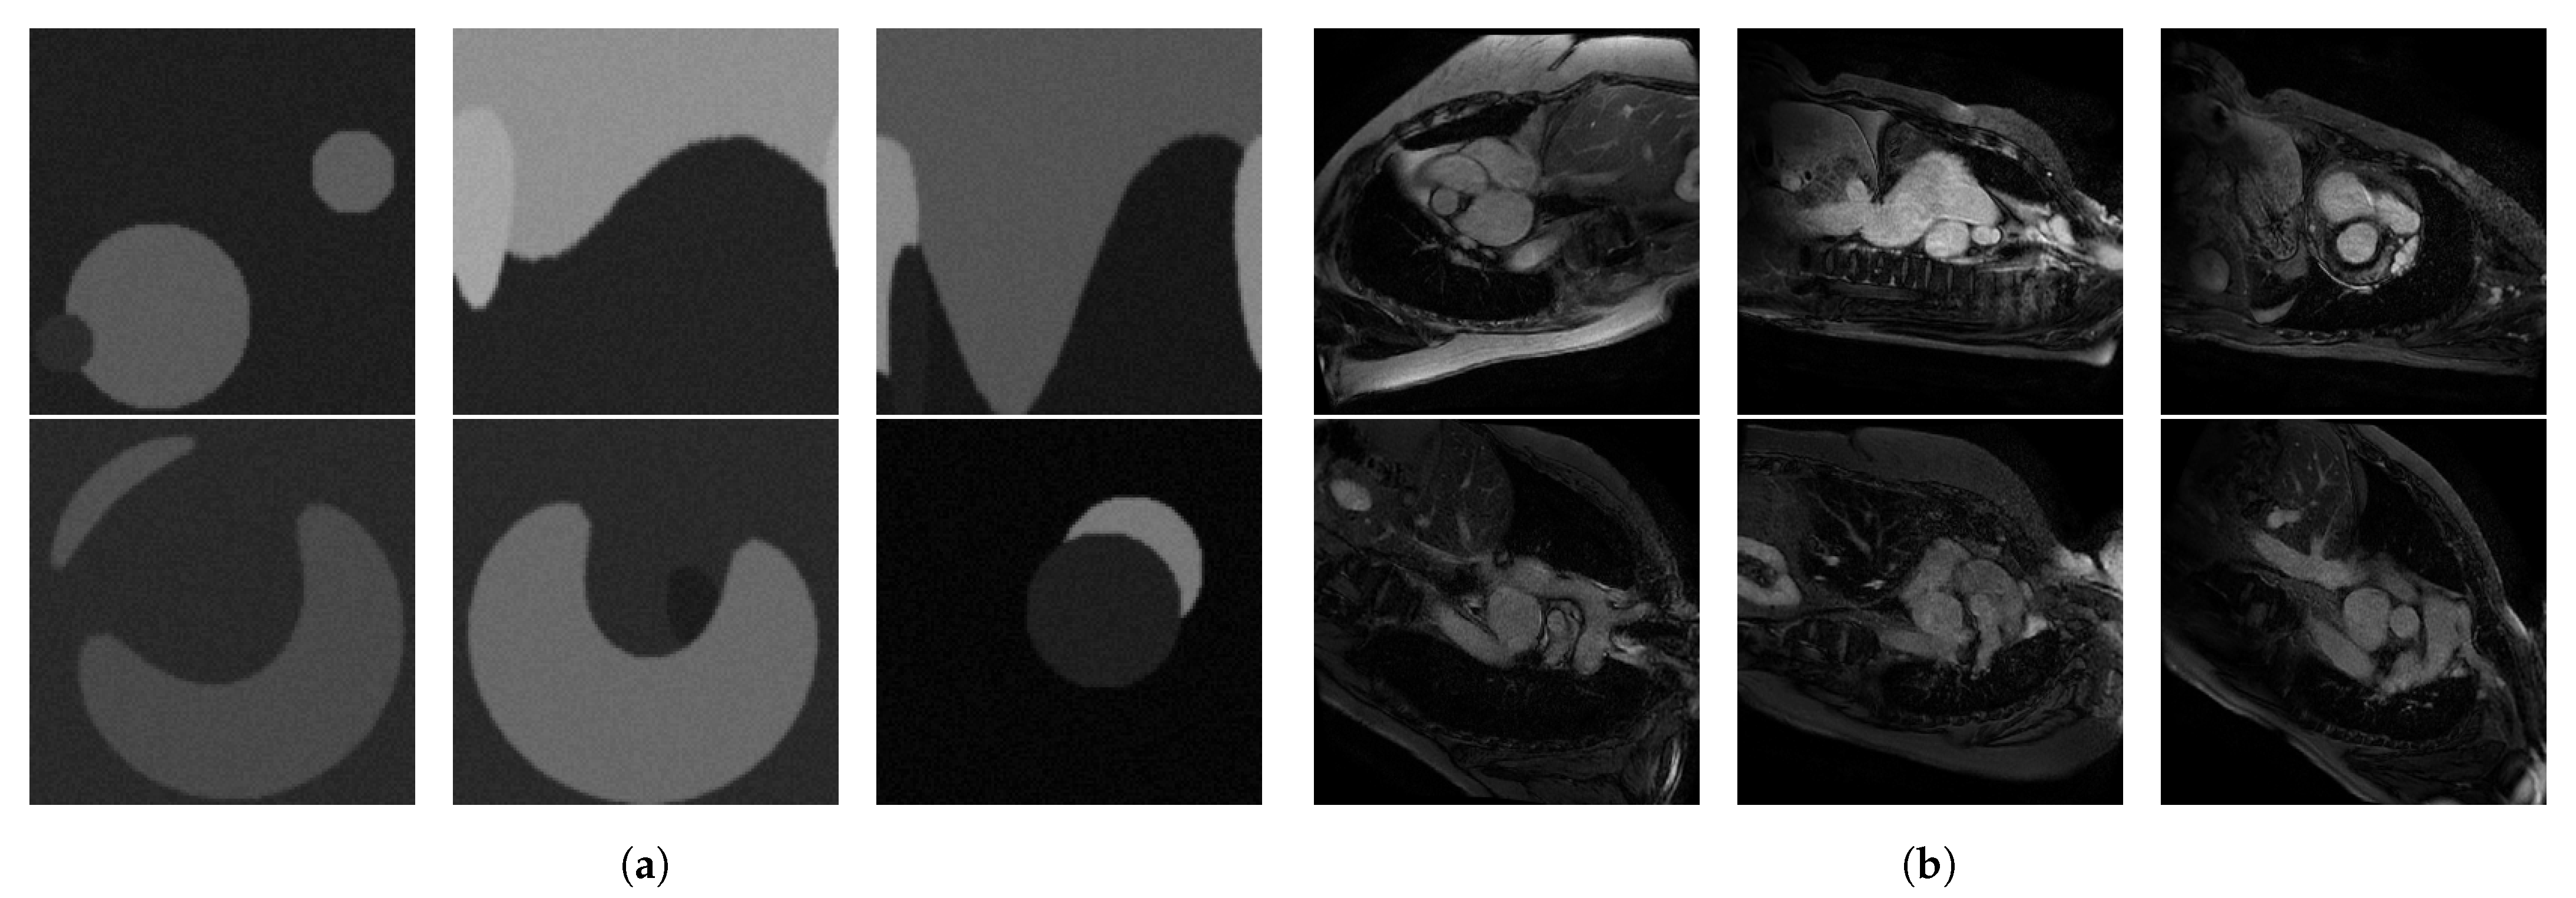

3.1. Experimental Setup

3.1.4. Dataset

3.2. Robustness Analysis

3.2.1. Comparing , and

4.1. Robustness Analysis

4.1.1. Comparing , , and